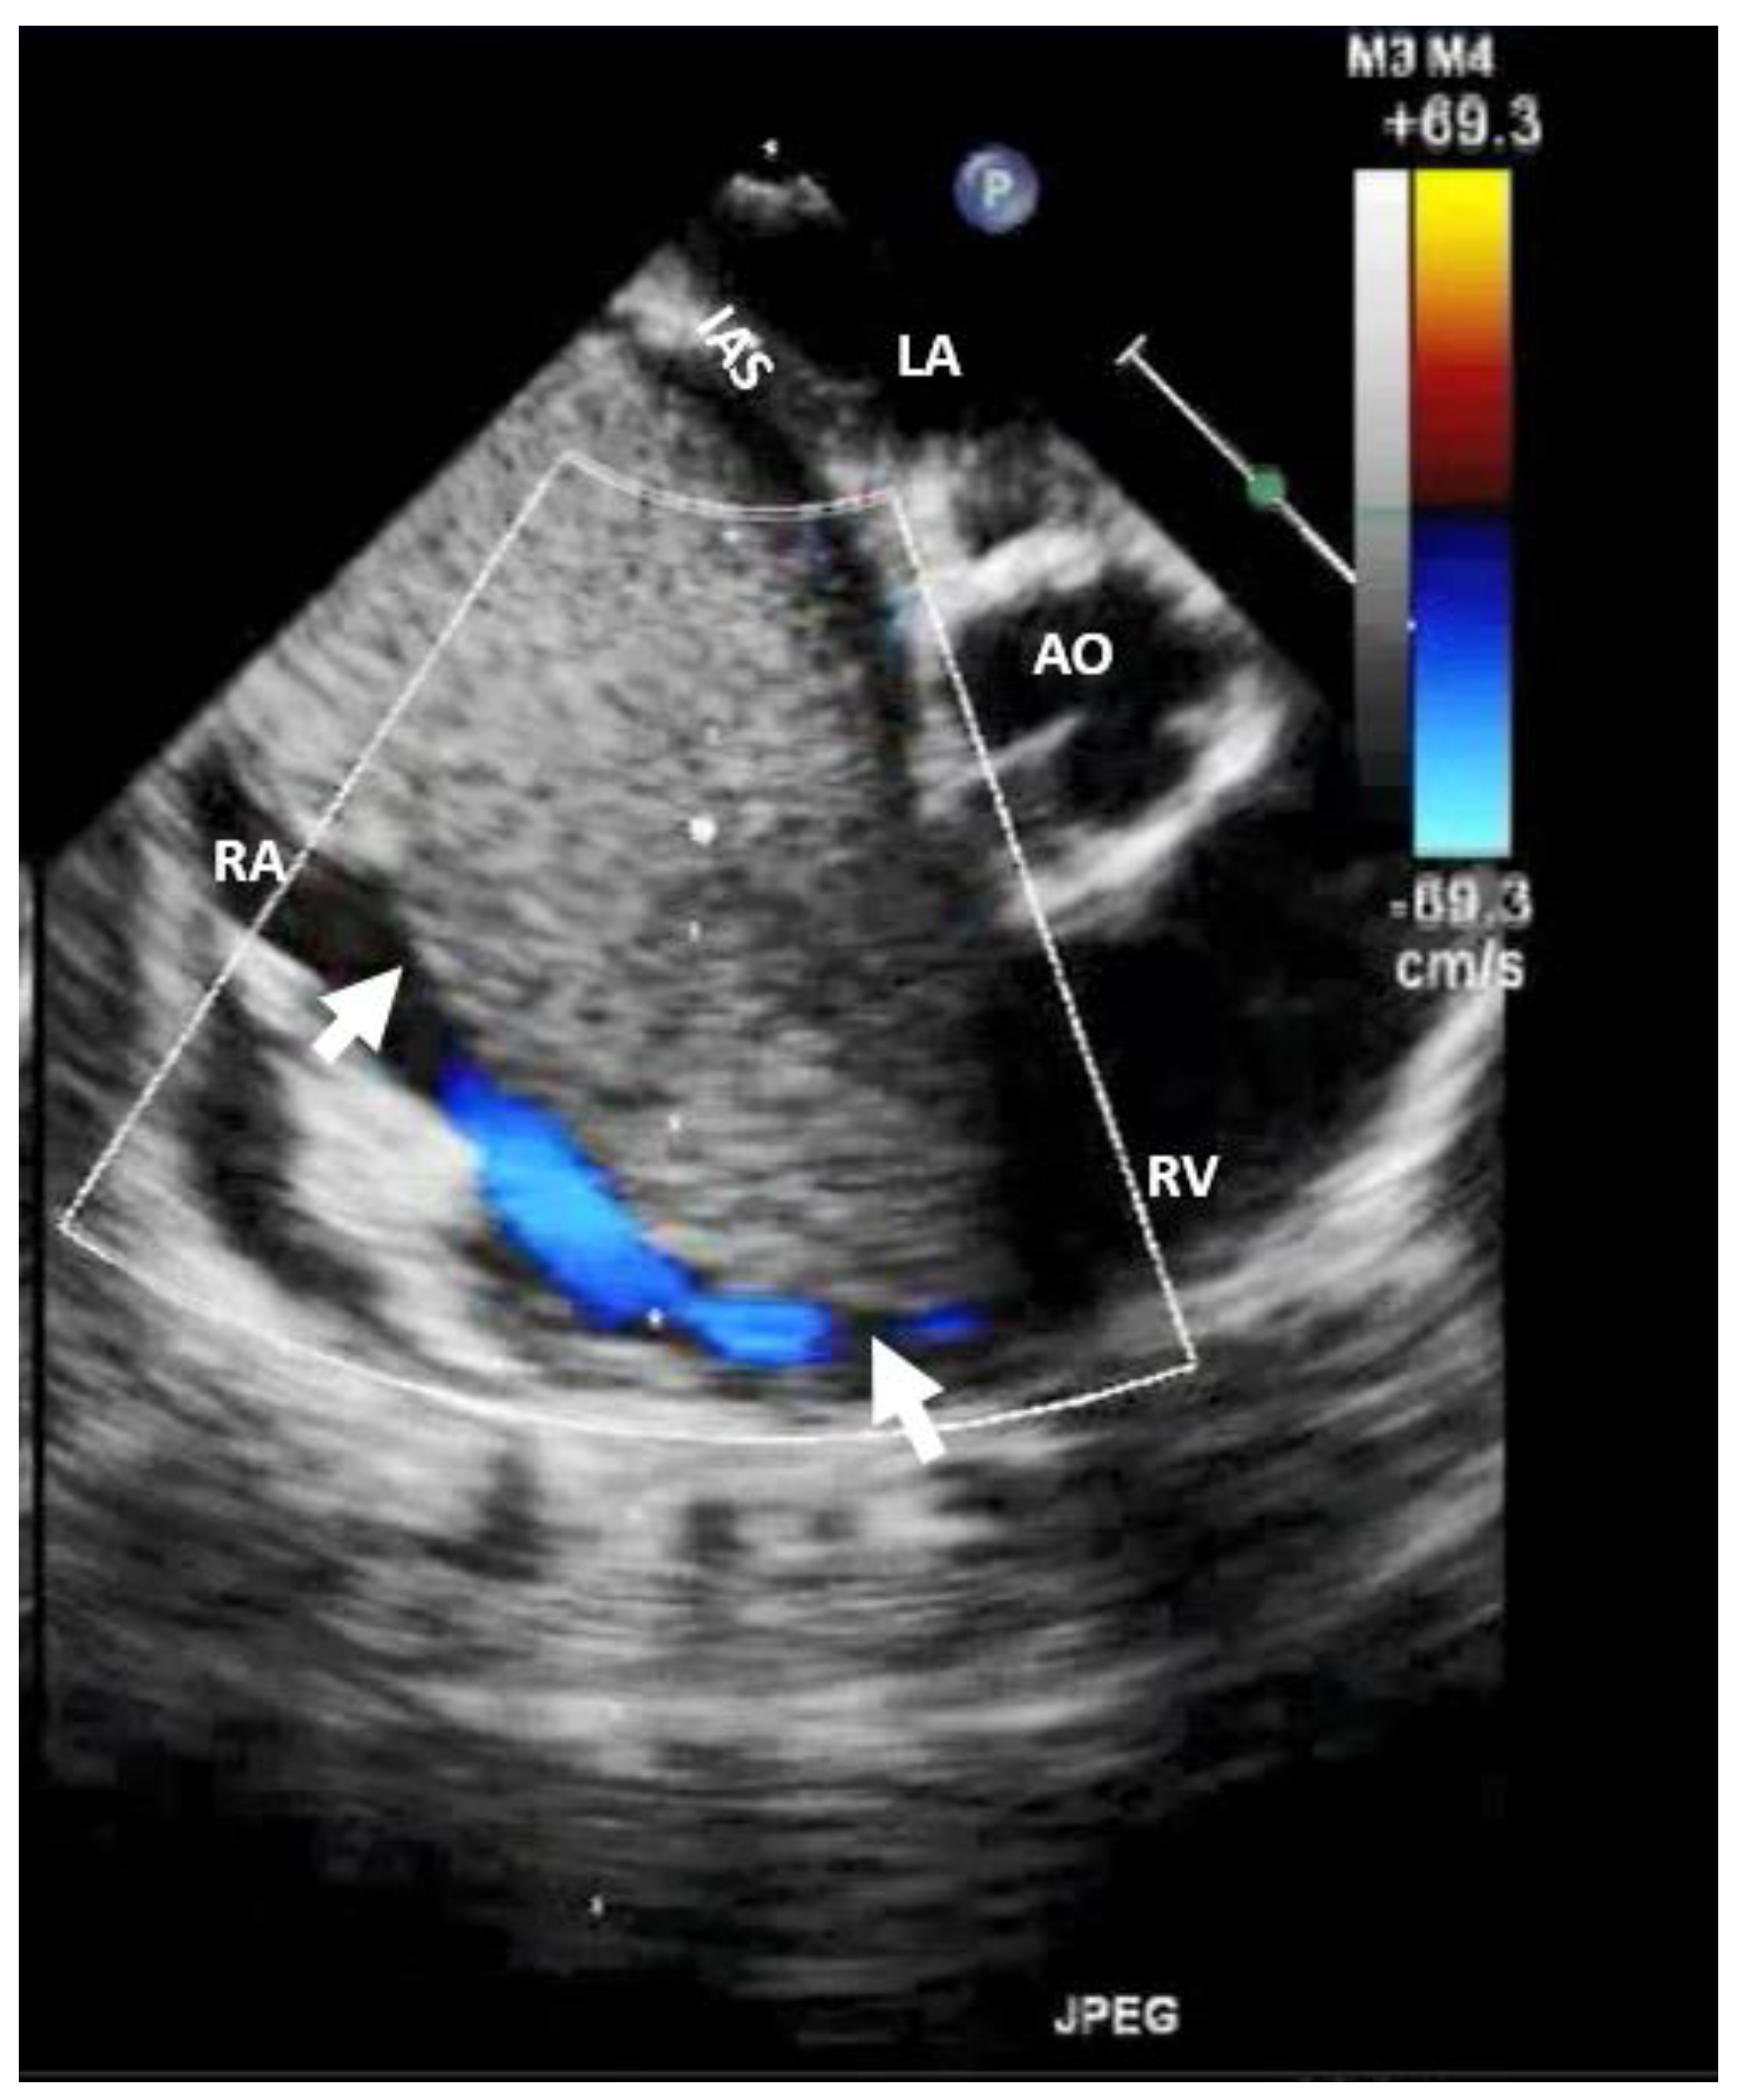

The diagnostic approach for right heart tumors is primarily based on differentiating them from other right heart masses such as thrombi (Figure 5) or vegetation (Figure 6). For example, in a patient known with neoplasia and port-a-cath (whether undergoing chemotherapy or not), a right heart masse discovered fortuity on TTE or TEE suggests, in a first step, a thrombus on the port-a-cath (Figure 5). It was less likely to be a benign tumor, especially considering these patients underwent repeated TTE evaluations. The initiation of anticoagulant treatment can determine the disappearing of this mass. However, a differential diagnosis is mandatory, involving considerations of marantic endocarditis or metastases.

Figure 5. Bi-dimensional transesophageal echocardiography (short axis view at the level of great vessels) showing a mass on the port-a-cath in a patient with neoplasia and chemotherapy. It was an incidental finding. This mass disappeared after anticoagulation treatment because it was a thrombus. AO, aorta; IVS, interventricular septum; LA, left atrium; LV, left ventricle; RV, right ventricle.